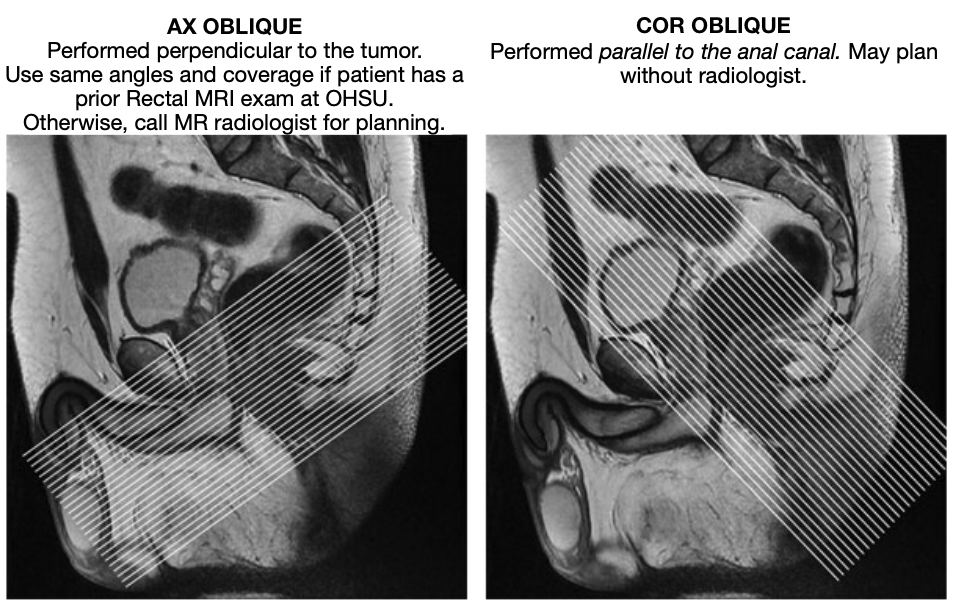

| AX Oblique | T2 | FSE | 3mm | 0mm | No | Fovea to Fovea | Inplane voxel size (acquired voxel size) is 0.6 x 0.6 mm. Add anterior sat band to reduce abdominal wall motion. Performed perpendicular to the tumor. Use same angles and coverage if patient has a prior Rectal MRI exam at OHSU. Otherwise, call MR radiologist for planning. |

| COR Oblique | T2 | FSE | 3mm | 0mm | No | Fovea to Fovea | Inplane voxel size (acquired voxel size) is 0.6 x 0.6 mm. Performed parallel to the anal canal. May plan without radiologist. |